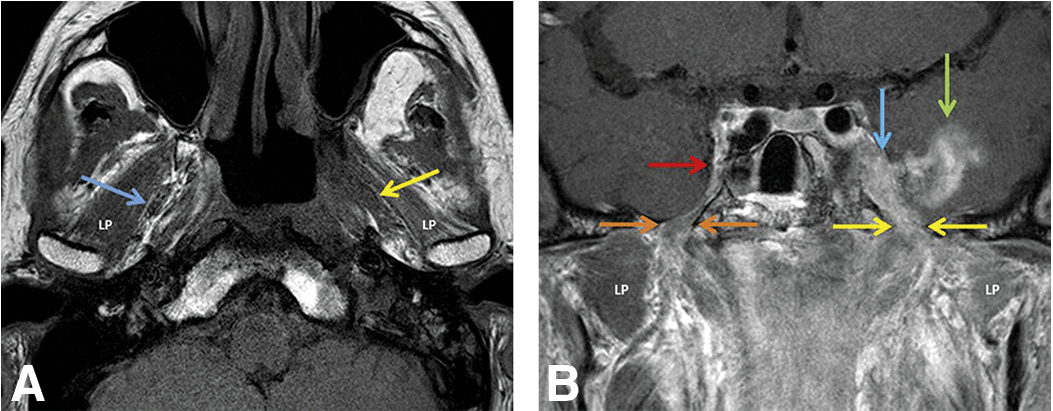

The trigeminal fat pad surrounds CN V3. Look for preservation of those straight lines in the medial masticator space between pterygoid muscles and venous plexus

Normal right fat pad and nasopharyngeal cancer spreading via the left into foramen ovale and Meckel cave: